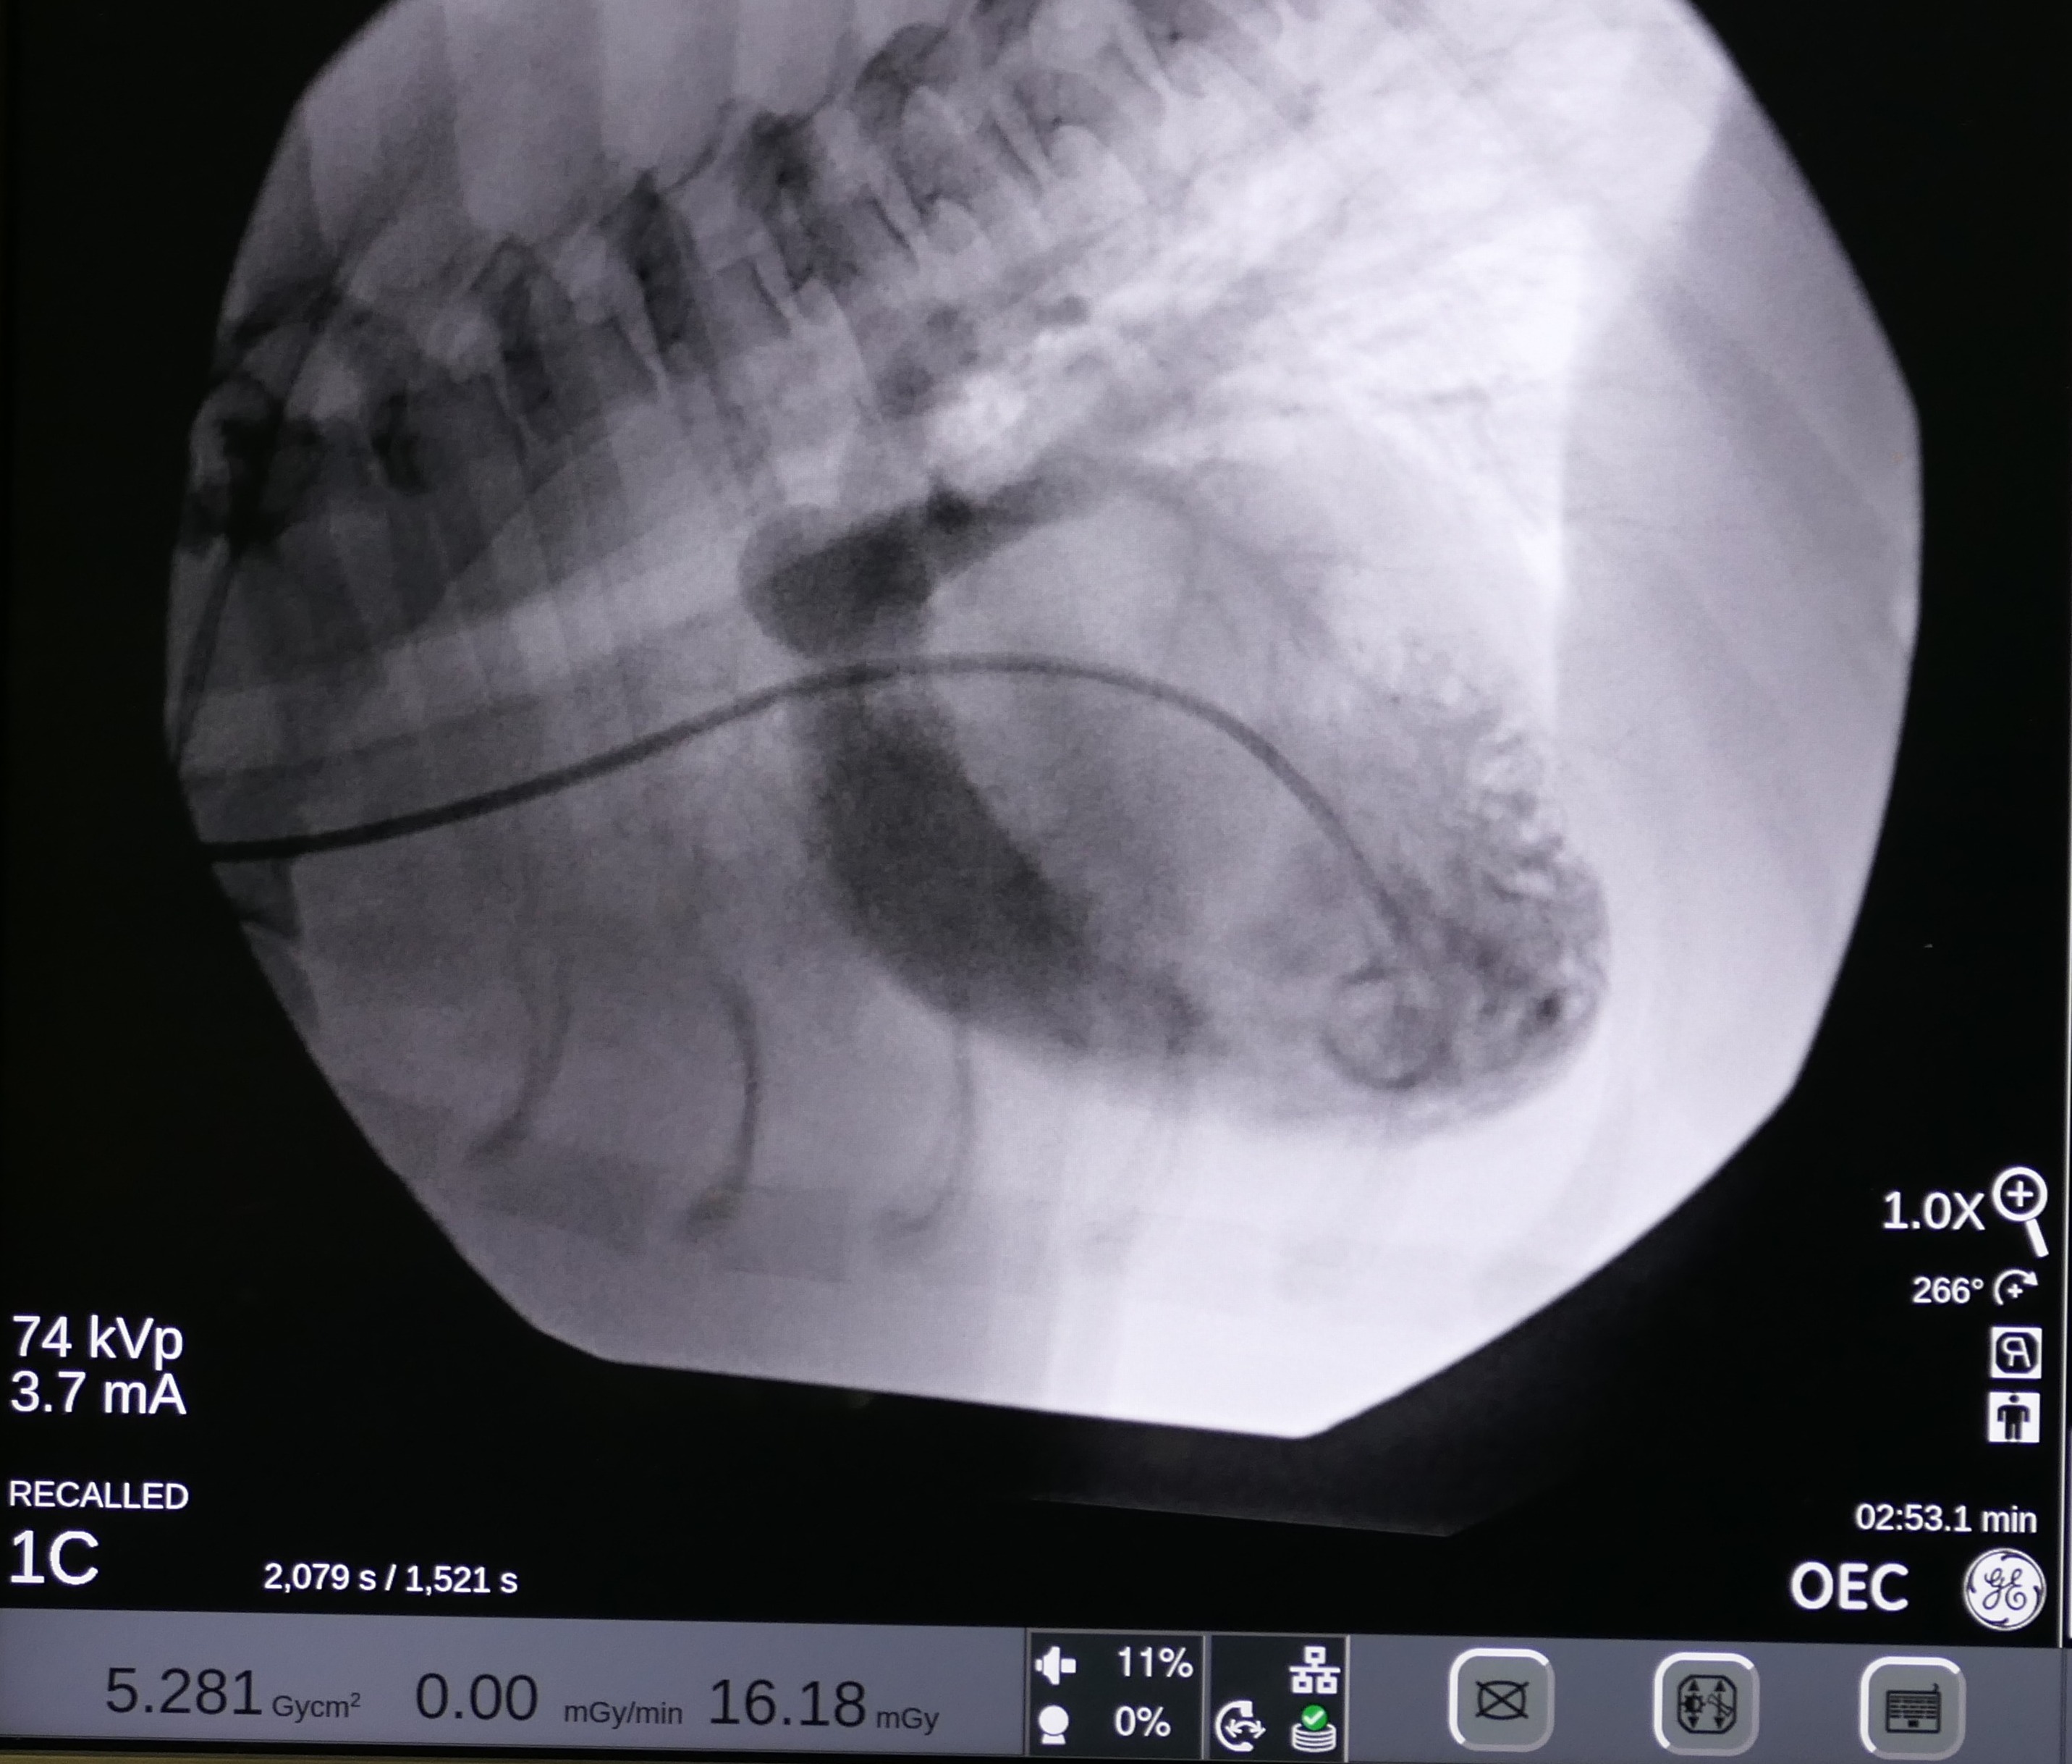

On May 7 2024, Snoop underwent a balloon valvuloplasty at MVRH. The procedure involved placing Snoop under general anesthesia and accessing the affected valve via the external right jugular vein. In order to gain access to the heart, a vascular introducer is first placed into the vein. This allows exchanging various wires and catheters without causing blood loss. Then, using fluoroscopy (Live X-rays) a catheter is advanced into the heart. This catheter has a small air balloon in its tip working as a “sail” and flowing downstream into the heart. Once the anatomy is assessed by using contrast, a Guire is placed to be used as a roadmap. Over this wire, a catheter with a large balloon in its tip is positioned across the fused valves. Once the balloon is inflated, the high pressures reached with this balloon separate the valve leaflets, decreasing the obstruction. This balloon reaches up to 18 atmospheres of pressure, and to put this in perspective, it is the equivalent of roughly stretching it with 260 pounds of force.